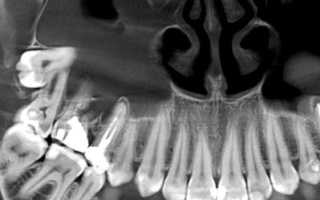

• панорамное костно-челюстное рентгенологическое сканированиепровести конусно-лучевую томограмму;

• сделать панорамное костно-челюстное рентгенологическое сканирование;

• выполнить точечный рентгенологический снимок зуба и прочее.